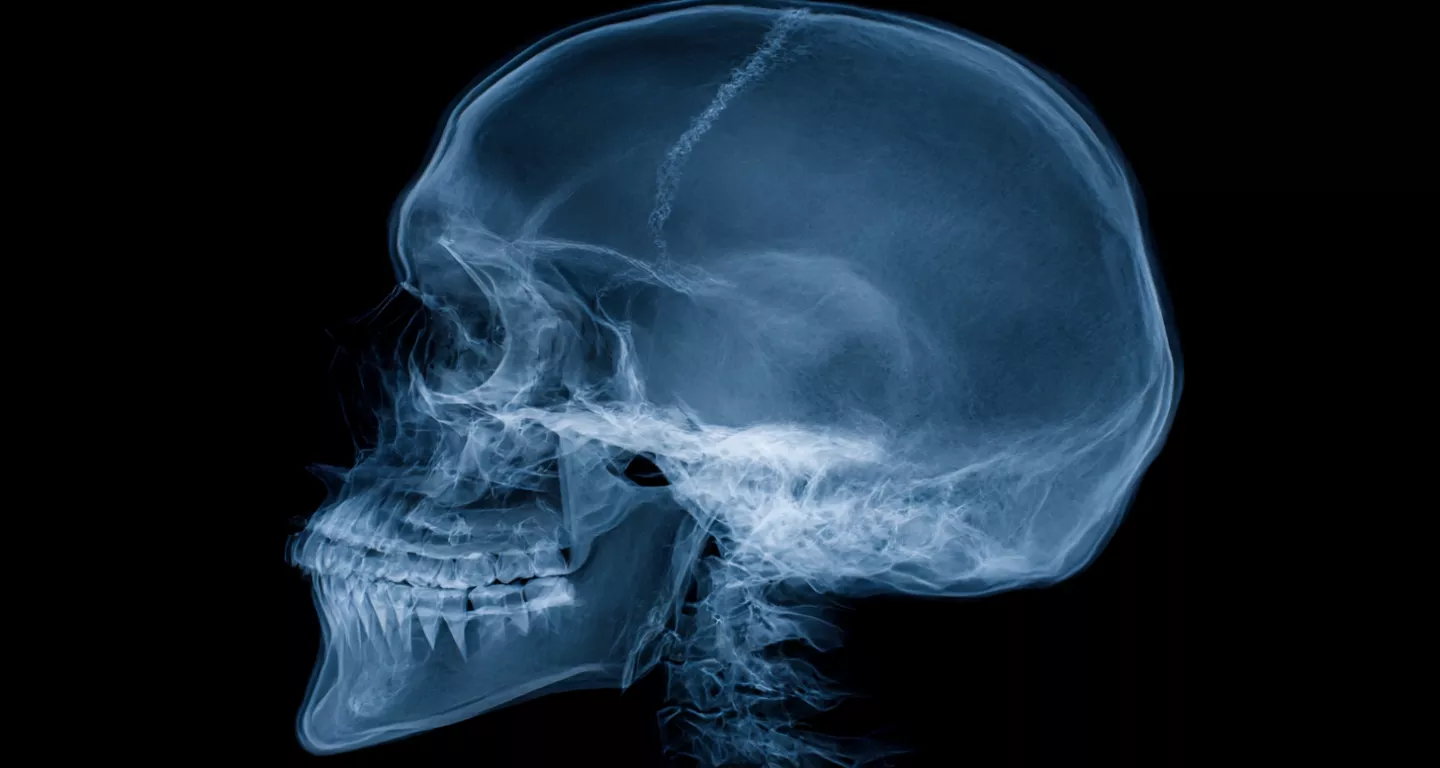

How a Traumatic Brain Injury Can Change Your Life — and Your Legal Options

Did an accident cause a traumatic brain injury? See how a TBI can change your life and what legal options you have for recovery.

A sudden accident—a car crash, a fall from a ladder, a slip on an unmarked wet floor—can end in a matter of seconds. Most people check for visible injuries: broken bones, bleeding, or bruising. But what happens when the most serious injury is invisible?

A traumatic brain injury (TBI) is often called a "silent epidemic" because its effects are not always immediate or obvious. Unlike a fractured arm, a TBI can fundamentally alter who you are. It can change your personality, erase memories, and steal your ability to work and interact with the world. Traumatic brain injuries (TBIs) are tragically common, underscored by recent CDC data: in just one year, these injuries led to over 214,000 hospitalizations and more than 69,000 deaths. For brain injury victims and their families, the path forward is often confusing and frightening, filled with medical appointments and mounting bills.

What Is a Traumatic Brain Injury? More Than Just a Bump on the Head

A traumatic brain injury occurs when a sudden, external force damages the brain. This can be a direct blow, a jolt (like in whiplash), or a penetrating injury. The damage happens in complex ways:

• Impact Injury: The brain may strike the inside of the skull (a "coup" injury) and then rebound, hitting the opposite side (a "contrecoup" injury).

• Diffuse Axonal Injury: During a violent rotation or shaking of the head, the brain's long connecting nerve fibers (axons) can be stretched and torn. This type of damage is widespread and often doesn't show up on standard CT scans or MRIs.

TBIs are generally classified as mild, moderate, or severe. A concussion is considered a "mild" TBI. However, this term is dangerously misleading. Any injury to the brain is serious, and even "mild" TBIs can have significant, lasting consequences.